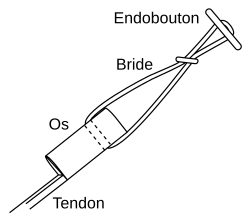

Tendon semi-tendineux

L'endobouton est tiré avec le transplant à travers le trou par le fil de traction, et ensuite fixé en tirant sur le fil de bascule.

Le muscle semi-tendineux tire sur la face interne de l'articulation du genou vers le fémur, et son tendon distal fait partie de ce que l'on appelle la « patte d'oie », qui est formée en outre par les tendons du muscle gracile et du sartorius.

Le transplant est obtenu par une section médiane sur le tibia, juste au-dessous du genou, au moyen d'un tendon stripper (décolleur de tendon), d'un ring stripper (décolleur en rond) ou encore d'un harvester (récolteur). Selon la longueur, le prélèvement sur le tendon est mis en triple ou en quadruple avec une certaine technique de couture, arrangé, noué et conduit par un trou dans le tibia jusqu'au fémur, où il est fixé de même. Depuis le début du XXIe siècle, on dispose d'une technique peu invasive pour le prélèvement plus facile et rapide sur le tendon au creux du genou, avec de meilleurs résultats cosmétiques[219].

Posé en quadruple, le semi-tendineux est plus solide que le tendon patellaire. Cette technique était de même valeur que celle du tendon patellaire jusqu'à peu près 2003. Depuis, cette technique s'est imposée comme « étalon-or », avant tout car le lieu de prélèvement se cicatrise avec moins de douleur. Quand le tendon semi-tendineux est trop court ou trop mince, on opère en plus un prélèvement sur le tendon gracile (technique STG : semi-tendineux et gracile ou technique DIDT en ancienne nomenclature: Droit Interne Demi-Tendineux ). Le transplant n'en est pas plus solide. Beaucoup de chirurgiens prennent toujours les deux tendons. En particulier pour la reconstruction du LCP, on a besoin à la fois du semi-tendineux et du gracile, ce qui rend nécessaire un prélèvement sur le genou opposé, particulièrement en cas de besoin de prélèvement supplémentaire pour intervention contre l'instabilité d'un ligament collatéral.

La technique opératoire la plus moderne est la technique du double faisceau (double bundle technique). Au moyen de quatre canaux dans l'os, deux faisceaux de tendons (antéromédial et postérolatéral) sont fixés dans le genou. Par une meilleure imitation de l'anatomie, les résultats produits sont plus stables. Par ailleurs ce procédé est techniquement plus exigeant, et n'est utilisé actuellement (2010) que dans quelques centres spécialisés. La fixation des deux transplants a lieu exclusivement hors de l'articulation par des endoboutons[220].

Le premier temps de l'opération est le prélèvement du transplant. Une incision d'environ 4 cm dans la peau sur la partie interne de la tête du tibia, au-dessus de la «patte d'oie» permet le prélèvement successif sur les tendons semi-tendineux et gracile. Les prélèvement sont faits sur les deux tendons avec un « couteau à tendon », et ont une longueur d'environ 28 cm. Ils sont pré-tendus avec un dispositif spécial, et cousus ensemble en un cordon multiple, par exemple quadruple. La longueur du transplant est alors de 7 cm, avec un diamètre d'environ 7 mm. Le transplant est alors cousu au moyen d'un fil spécial dans les deux trous internes d'un disque ovale à quatre trous (endobouton). Ce fil spécial n'est pas résorbable.

Enfilage du transplant